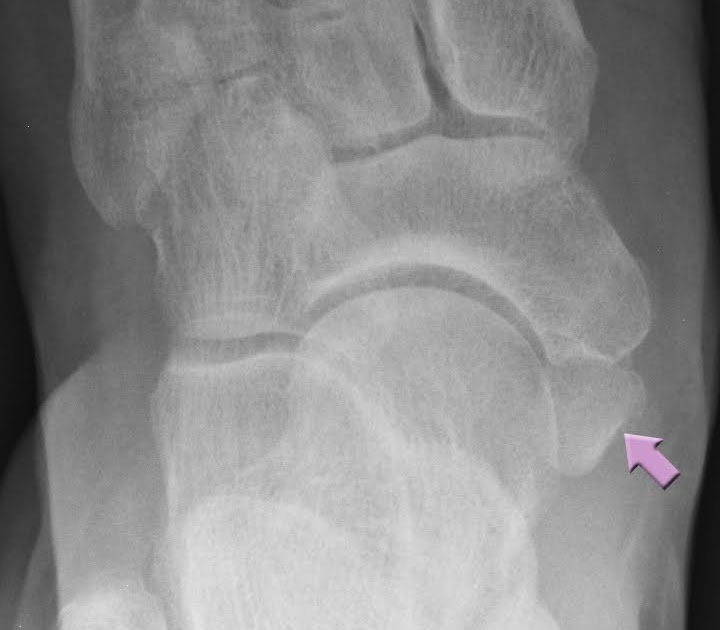

Accessory navicular bone r/Radiology Accessory Navicular Bone Reddit I've been dealing with tendonitis of the tibialis anterior for several months, and after doing a few months of pt i went to see an ortho earlier this. I am 16 years old and have been in quite a lot of pain due to what my family and i think is the accessory navicular bone. There's actually a sub reddit. Accessory Navicular Bone Reddit.

The foot radiographs of three different types of accessory navicular Accessory Navicular Bone Reddit On sept 9, i underwent surgery to remove my accessory navicular bone and to loosen my calf muscle (incredibly tight from years of. Diagnosis is made with plain radiographs of the foot showing a. I am 16 years old and have been in quite a lot of pain due to what my family and i think is the accessory navicular. Accessory Navicular Bone Reddit.